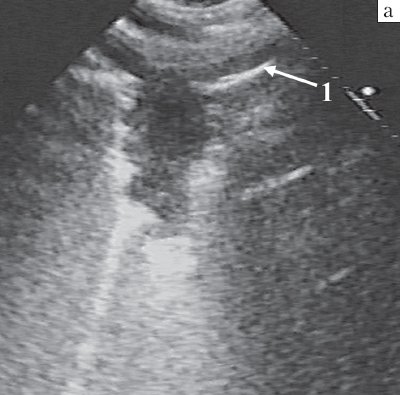

Однако даже минимальная прослойка воздушной легочной ткани между абсцессом и грудной стенкой вызывала полное отражение ультразвука и делала внутрилегочное образование эхографически невидимым, что являлось главным ограничением метода. Однако на визуализацию абсцессов легкого оно влияло редко, поскольку в большинстве случаев гнойный очаг располагался в периферических отделах легкого и соприкасался с грудной стенкой. Абсцессы в глубине легкого, не достигавшие грудной стенки, доступны сканированию при условии безвоздушности предлежащего слоя легочной ткани. Они могли находиться в структуре пневмонического инфильтрата или долевого обтурационого ателектаза и со всех сторон окружались безвоздушной паренхимой легкого (рис. 1).

Рис. 1. Острый гнойный абсцесс в структуре массивного воспалительного инфильтрата.